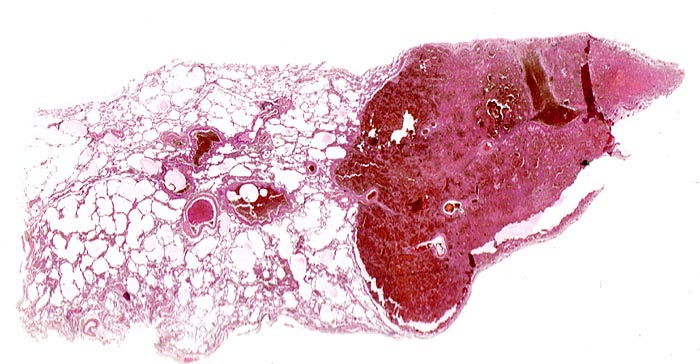

Makroskopisch bilden sie ein Dreieck mit der Basis an der Pleuraoberfläche, sind leicht erhaben, dunkelrot gefärbt und induriert. Innerhalb von 48 Stunden beginnen die Erythrozyten zu zerfallen und der Infarkt wird von aussen her narbig organisiert.

• Scharf begrenzte dreiecksförmige hämorrhagische Nekrose des Lungenparenchyms.